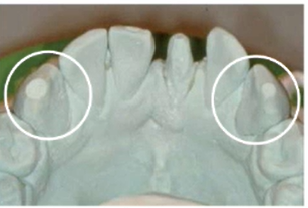

Lingual pull

Cause: exceeding working time, tray movement after seating, insuffiecient amount of impression material

Solution: follow manufacturers working time or use different material with longer working time, don’t move after seating, use more material

Tray tooth contact

Caused by: tray too small, insufficient material

Solution: test various sizes of tray, fill adequately

common with disposable trays